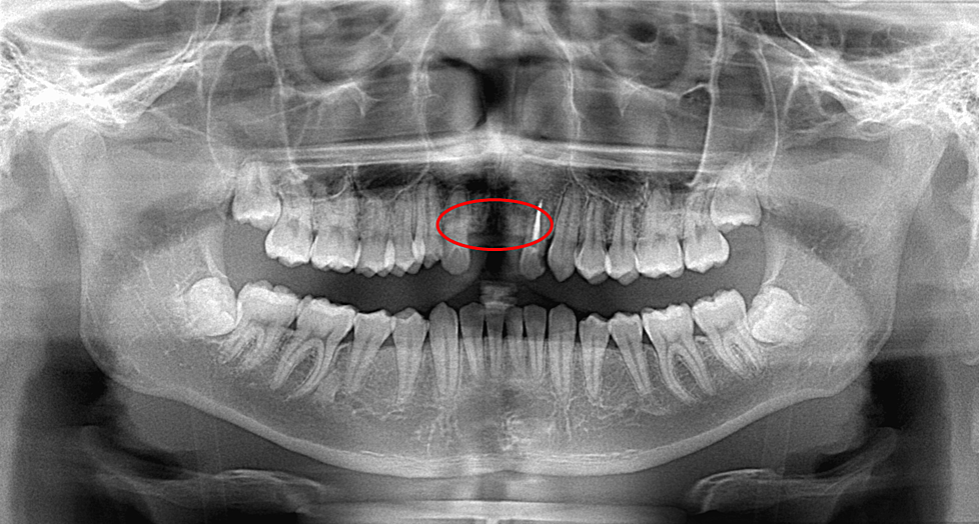

The success of this case study hinged on meticulous planning and advanced technology. Doctors used a 3D-printed replica of the patient’s wisdom tooth to visualize the exact positioning and ensure a perfect fit in the upper jaw where the front teeth were missing. This 3D model helped create a surgical guide, ensuring a smooth and precise procedure.

From Haneda Y, Murayama T, Nikawa H, et al., Wisdom Tooth Autotransplantation for the Missing Maxillary Central Incisors Using a 3D-Printed Replica: A Case Report, Cureus, May 29, 2024, vol. 16, no. 5.

The wisdom tooth autotransplantation involved extracting the patient’s lower right wisdom tooth and transplanting it into the upper jawbone. After the surgery, the transplanted tooth was stabilized with splinting, and orthodontic treatment was implemented to adjust its position and alignment with the surrounding teeth.